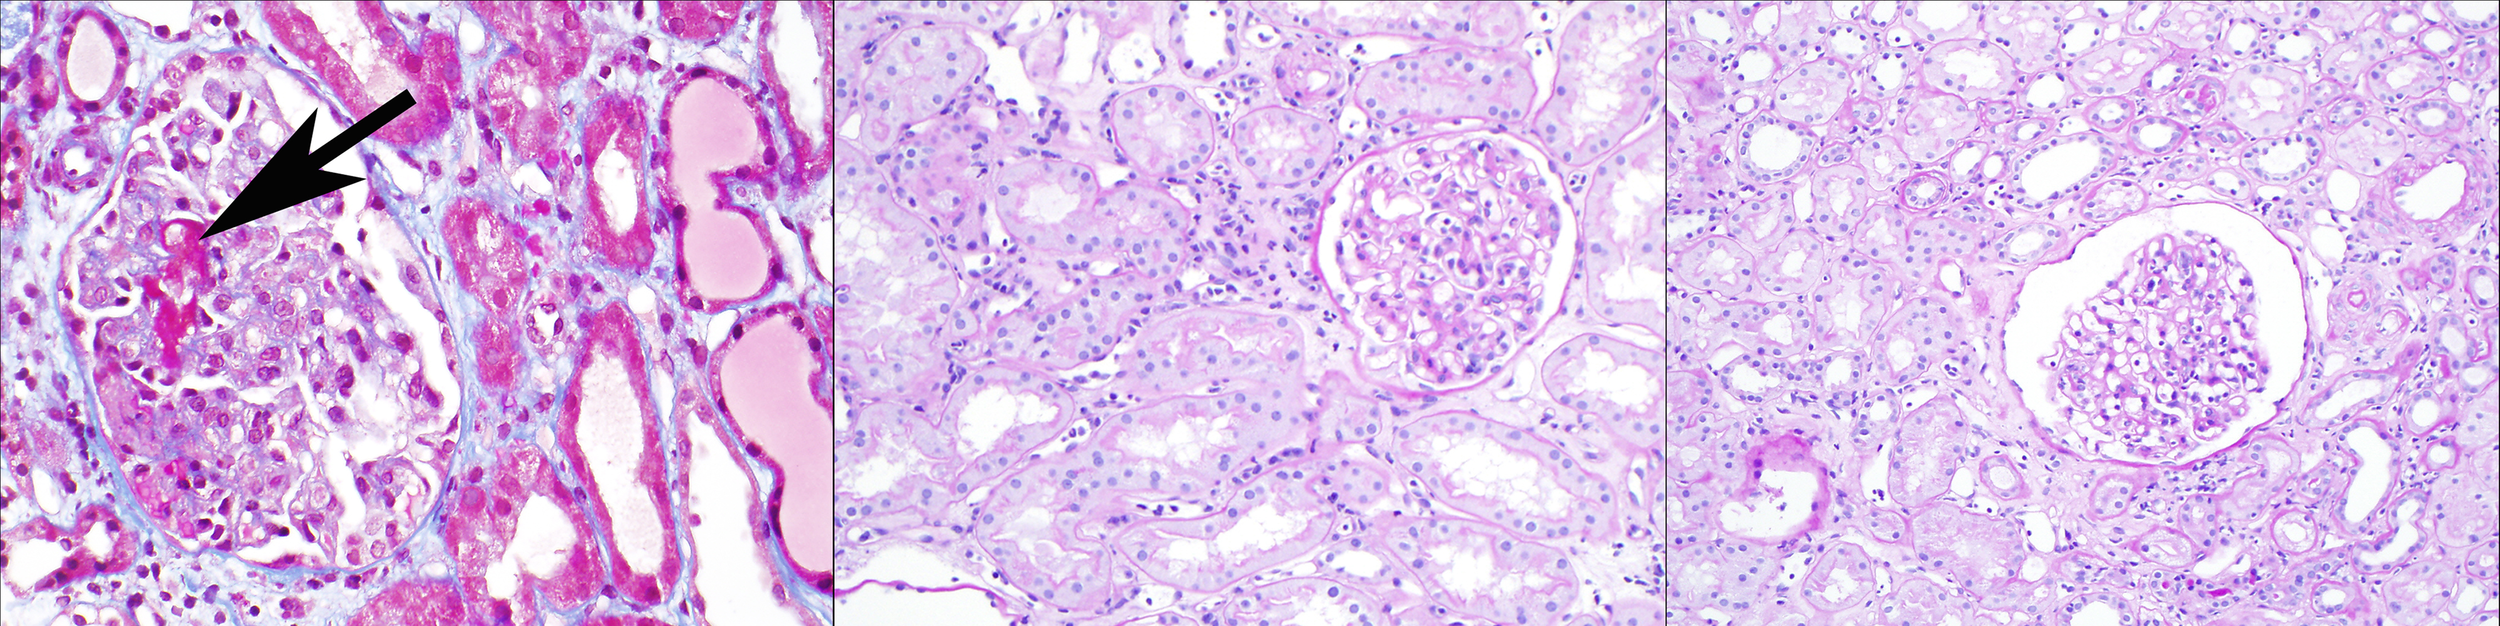

Histologically, these cases of early acute ABMR with high serum DSA levels often show an “ATN-like” (acute tubular necrosis) phenotype (Banff “grade 1”) with few marginated inflammatory cells (particularly neutrophils) in glomerular and peritubular capillaries, along with glomerular thrombi (see Figure 1, left panel). Some cases do show moderate microvascular inflammation (g + ptc >/=2), particularly when the pathologist is aware of the clinical consideration of acute ABMR as a diagnostic possibility with therapeutic implications (Banff “grade 2”) (11, 17, 18). These early acute ABMR biopsies are essentially always C4d positive, and C4d positivity correlates with the serum DSA level (11). It should be noted that the capillary inflammation does not mirror the clinical severity of this ABMR manifestation: a higher Banff capillaritis score does not indicate a more severe acute rejection phenotype. In this way, ABMR is different from acute cellular rejection, tubulointerstitial type (Banff grade IA or IB or borderline rejection), where more extensive inflammation with a higher Banff i or t score reflects a more severe rejection (19).

Figure 1

Three clinicopathologic phenotypes of ABMR, one Banff diagnosis: In the left panel (Masson trichrome stain), a patient 2 weeks after positive-crossmatch kidney transplant has acute kidney injury; the biopsy shows glomerular thrombi, acute tubular injury, and minimal capillaritis, and diffuse C4d deposition in peritubular capillaries. In the middle panel (periodic acid Schiff stain), a patient 4 months after positive-crossmatch kidney transplant has stable graft function and undergoes protocol biopsy; the biopsy shows glomerulitis and peritubular capillaritis; C4d staining is negative. In the right panel (periodic acid Schiff stain), a patient 2 years after kidney transplant has stable graft function and undergoes protocol biopsy; the biopsy shows glomerulitis and peritubular capillaritis; C4d staining is negative. All of these biopsies pictured would be assigned the Banff diagnosis of “active ABMR”, although clearly the clinical settings are different.